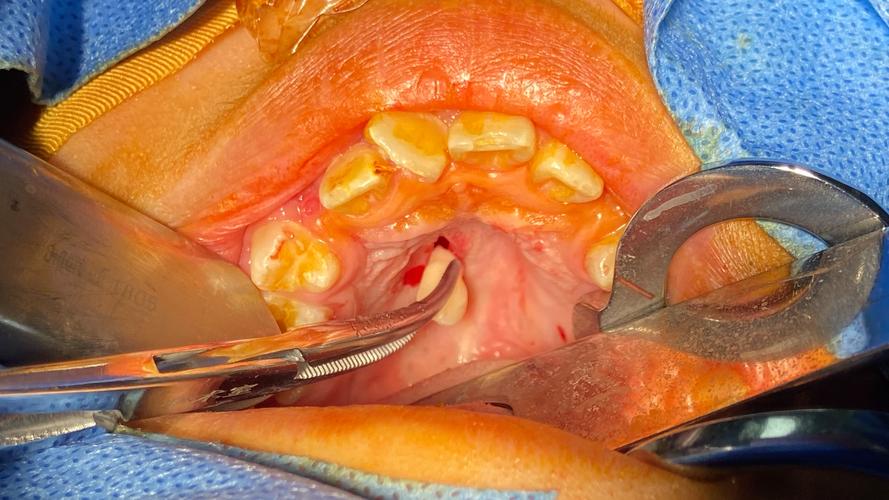

暴露与松动多生牙

- 暴露牙冠: 去除足够骨质后,暴露多生牙的牙冠。

- 微创器械应用:

- 微创拔牙挺: 使用薄而锋利的挺(如Molt挺、三角挺、直挺),轻柔、精细地插入牙冠与骨壁之间的间隙,利用楔力和轻微的旋转力进行松动。避免使用杠杆力,防止损伤邻牙或骨壁。

- 分根技术: 如果多生牙牙根弯曲、分叉或与邻牙粘连,可能需要使用高速手机或超声骨刀在根分叉处或靠近牙根处进行分根,将其分成2-3个部分分别拔除,这能大大降低拔除难度和风险。

- 根挺: 对于已松动或部分脱出的牙根,使用根挺小心地将其挺出或拔出。

取出多生牙

- 三角钳/取根钳: 使用精细的取根钳夹住已松动或分根后的牙体部分,轻柔、持续地旋转、牵引拔除,避免暴力摇晃。